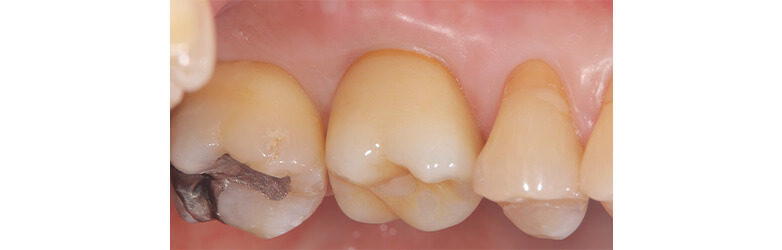

上の前歯の古い被せ物を治したいと言うことで来院されました。上下の前歯は少しガタガタになっており、奥歯には古い金属の詰め物が見られます。

上の前歯の被せ物が長い期間保つようにするためには、下の前歯のガタガタを整えておく必要があります。この症例くらいのガタガタであれば、インビザラインGoを使えば短期間で綺麗に治すことができます。歯並びが整ったことで治療のモチベーションが上がり、ホワイトニングと奥歯の銀歯を全てセラミックに置き換える治療を行い、金属がない(ノンメタル)状態になりました。

マウスピース矯正は装着時間が大切になるため、指示通り装着いただけないと予定通りの効果が得られない場合があります。

1年半

138万円(税込)

古い被せ物を除去した際、虫歯が大きいと抜歯になるリスクがございます。